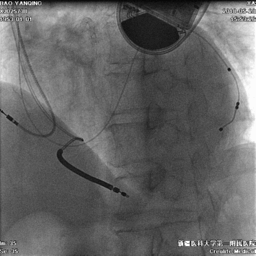

电极植入

● 延PTCA导丝送入电极至远端。

● 植入心房电极和右室除颤电极,连接起搏器。

术中电参数

● 术中测试除颤电极感知良好,除颤阻抗正常。

➛心房:

0.8V/0.42ms,Pwave:5mv,阻抗:420欧姆

➛心室:

0.8V/0.42ms,Rwave:>20mv,阻抗:600欧姆

➛左室:

LV-tip 0.8V/0.42ms 阻抗:640欧

LV-2 1.25V/0.42ms 阻抗:600欧

LV-3 1.5V/0.42ms 阻抗:650欧

LV-4 1.0V/0.42ms 阻抗:700欧